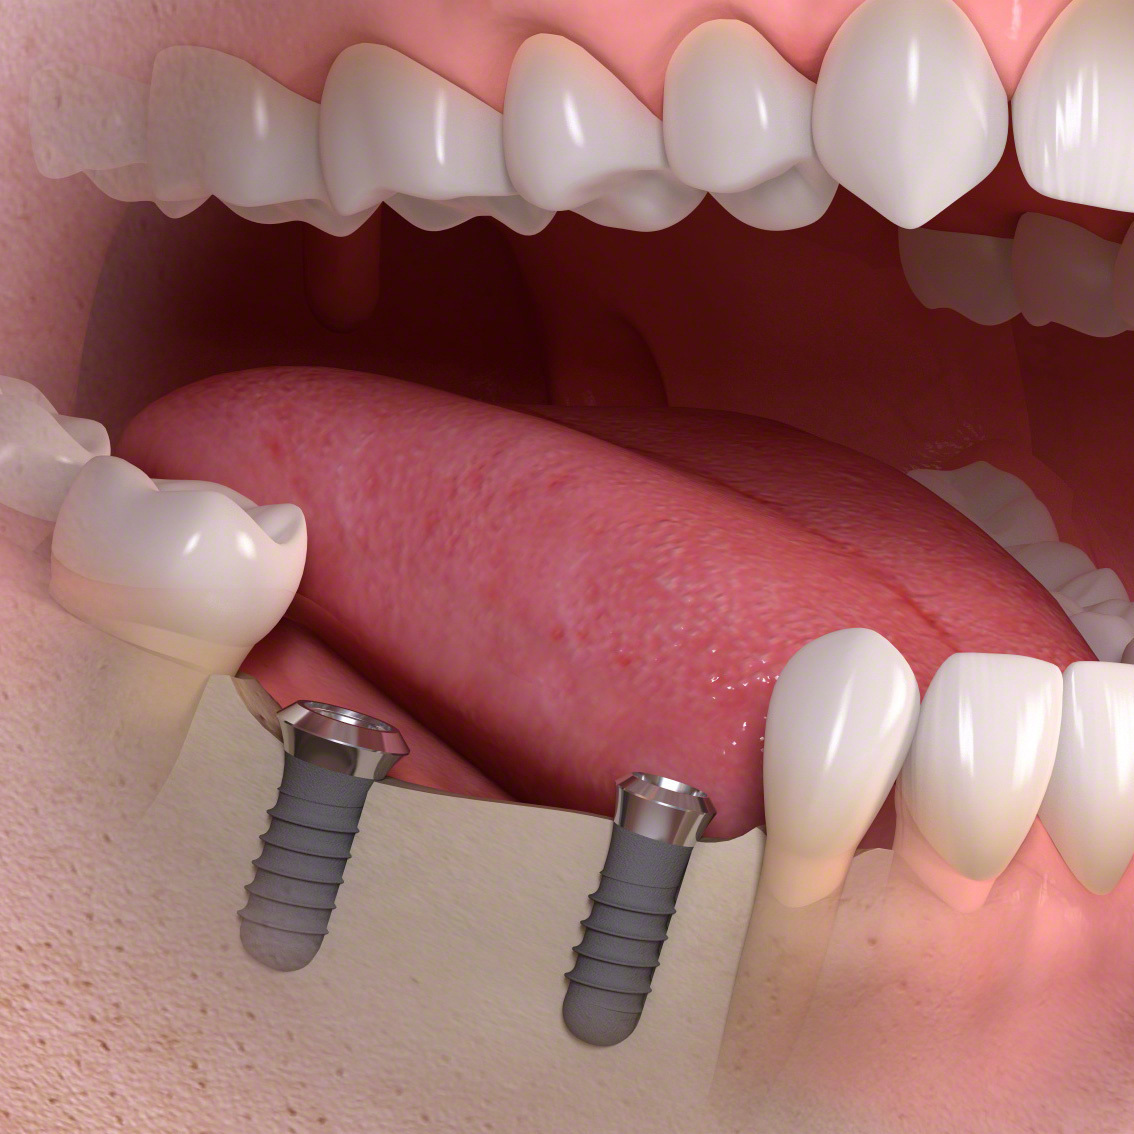

インプラントとは?

(通常のインプラント法)

歯科インプラントとは、歯を失った部分に人工歯根(主にチタン製)を外科的に埋め込み、その上にセラミックなどで作られた人工の歯を取り付けて、機能と見た目を回復する治療法です。

その後、一次手術としてインプラント体(フィクスチャー)を顎の骨に埋入し、数か月の治癒期間を経て骨としっかり結合させます。治癒後には二次手術を行い、歯肉からインプラントの上部構造を露出させます。なお、骨や歯肉の状態が良好な場合には、一次手術と二次手術を同時に行う「1回法」が選択されることもあります。

傷口が治った後に精密な型取りを行い、上部構造(人工歯)を製作・装着します。